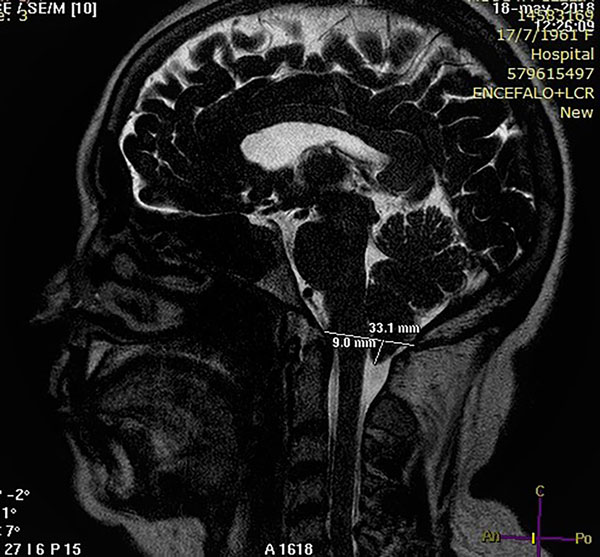

Caso 1: Cefalea como único síntoma

Una mujer de 57 años de edad consultó por cefaleas de 8 meses de evolución. Las cefaleas eran fronto occipitales, opresivas, de frecuencia diaria y aumentaban con el movimiento. No refirió aumento del dolor por tos o esfuerzos. El examen neurológico fue normal. La RM mostró un descenso amigdalino de 9 mm (Figura 3). Se le solicitó una RM en contraste de fase para estudiar la dinámica de LCR en la charnela occipito-cervical. Las velocidades de circulación del LCR fueron normales. Se decidió no operarla y fue referida a Neurología en donde hicieron el diagnóstico de cefalea tensional; fue tratada con ergotamínicos y ansiolíticos y la cefalea cedió. La paciente sigue bajo control y luego de 2 años de seguimiento la mejoría se mantiene.

Figura 3: Caso 1. Imagen sagital de RM de cerebro ponderada en T2 de alta resolución que muestra un descenso amigdalino de 9 mm.